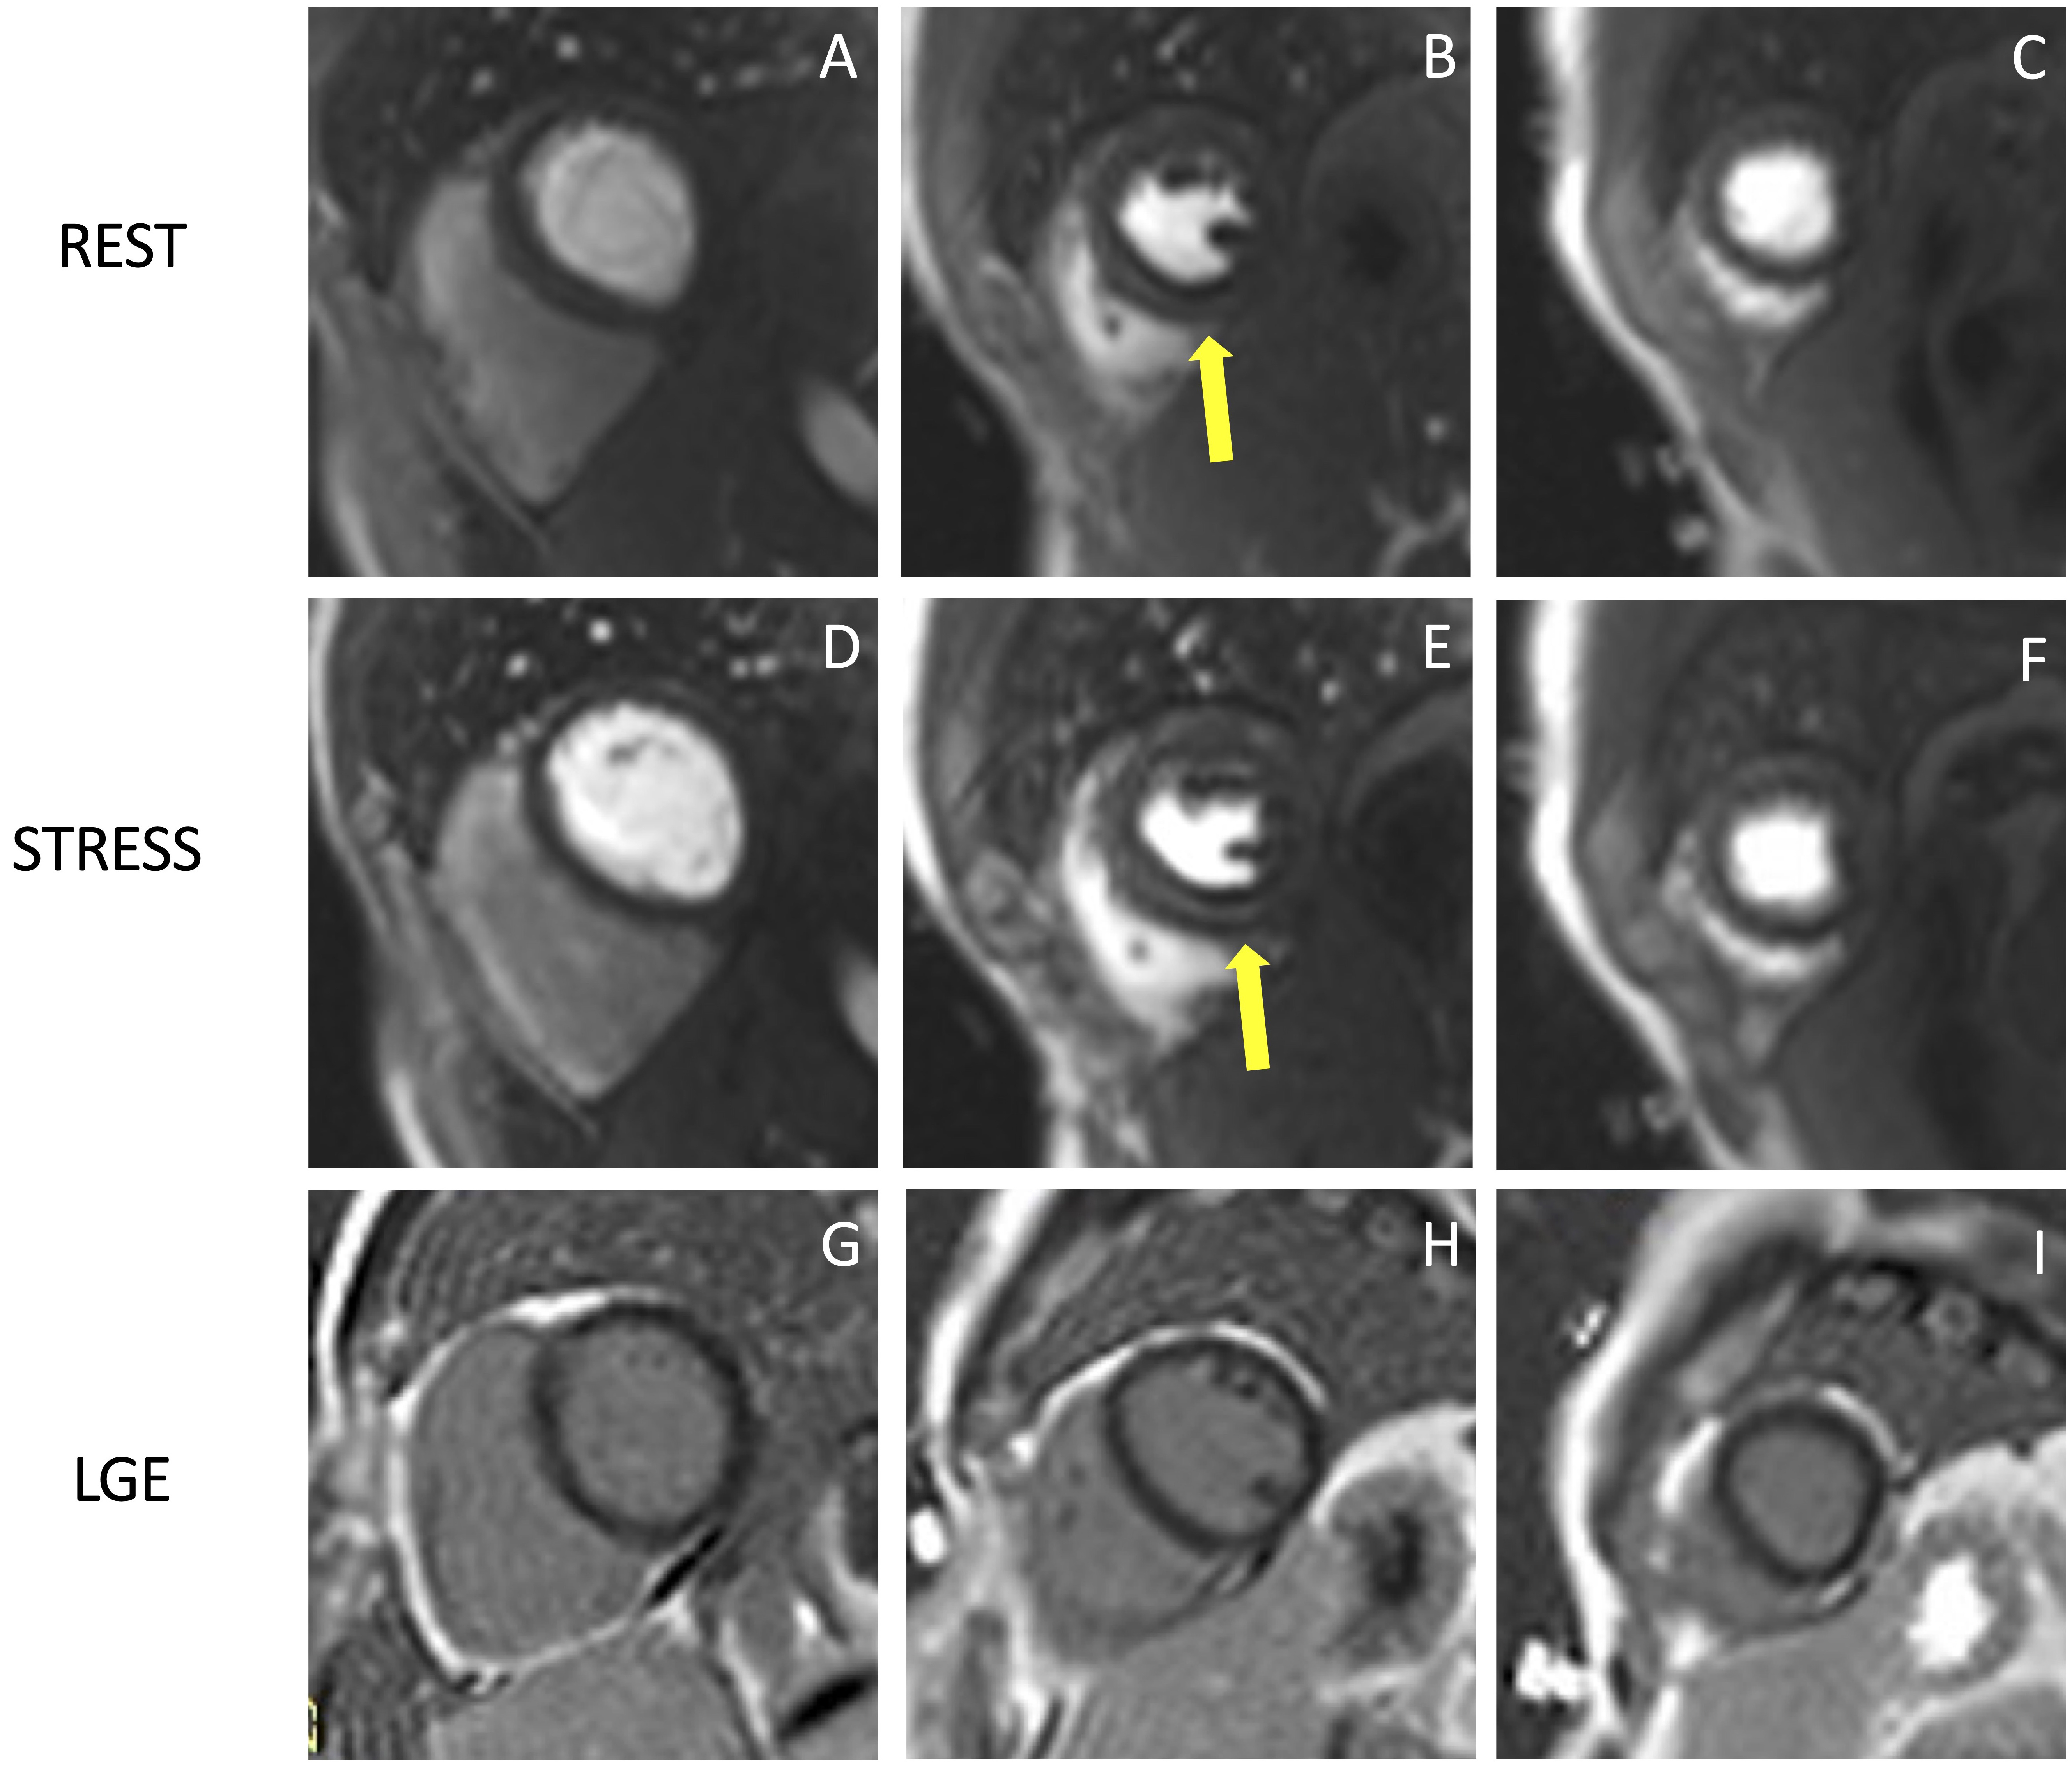

Fig. 5.Example of CMR adenosine-stress perfusion in the presence of

ischemic scar. This is the case of a 68-year-old man with a history of subacute

myocardial infarction and previous unsuccessful percutaneous angioplasty on the

RCA. Short axis rest and stress perfusion images are shown respectively at the

basal (A,D), mid-ventricular (B,E), and apical (C,F) level. There is

evidence of hypoperfusion, appearing as a hypointense subendocardial area in the

inferior septum, inferior wall and in the mid portion of the anterior wall

(yellow arrow heads). Corresponding LGE images (G,H,I) show ischemic scars

(yellow arrow lines) with a transmural distribution in the inferior septum and

inferior wall. Moreover, there is subendocardial LGE with a 50–75%

transmurality in the anterior wall. The perfusion defects appear both in the rest

and stress images and are related to the presence of non-viable myocardium (scar

transmurality